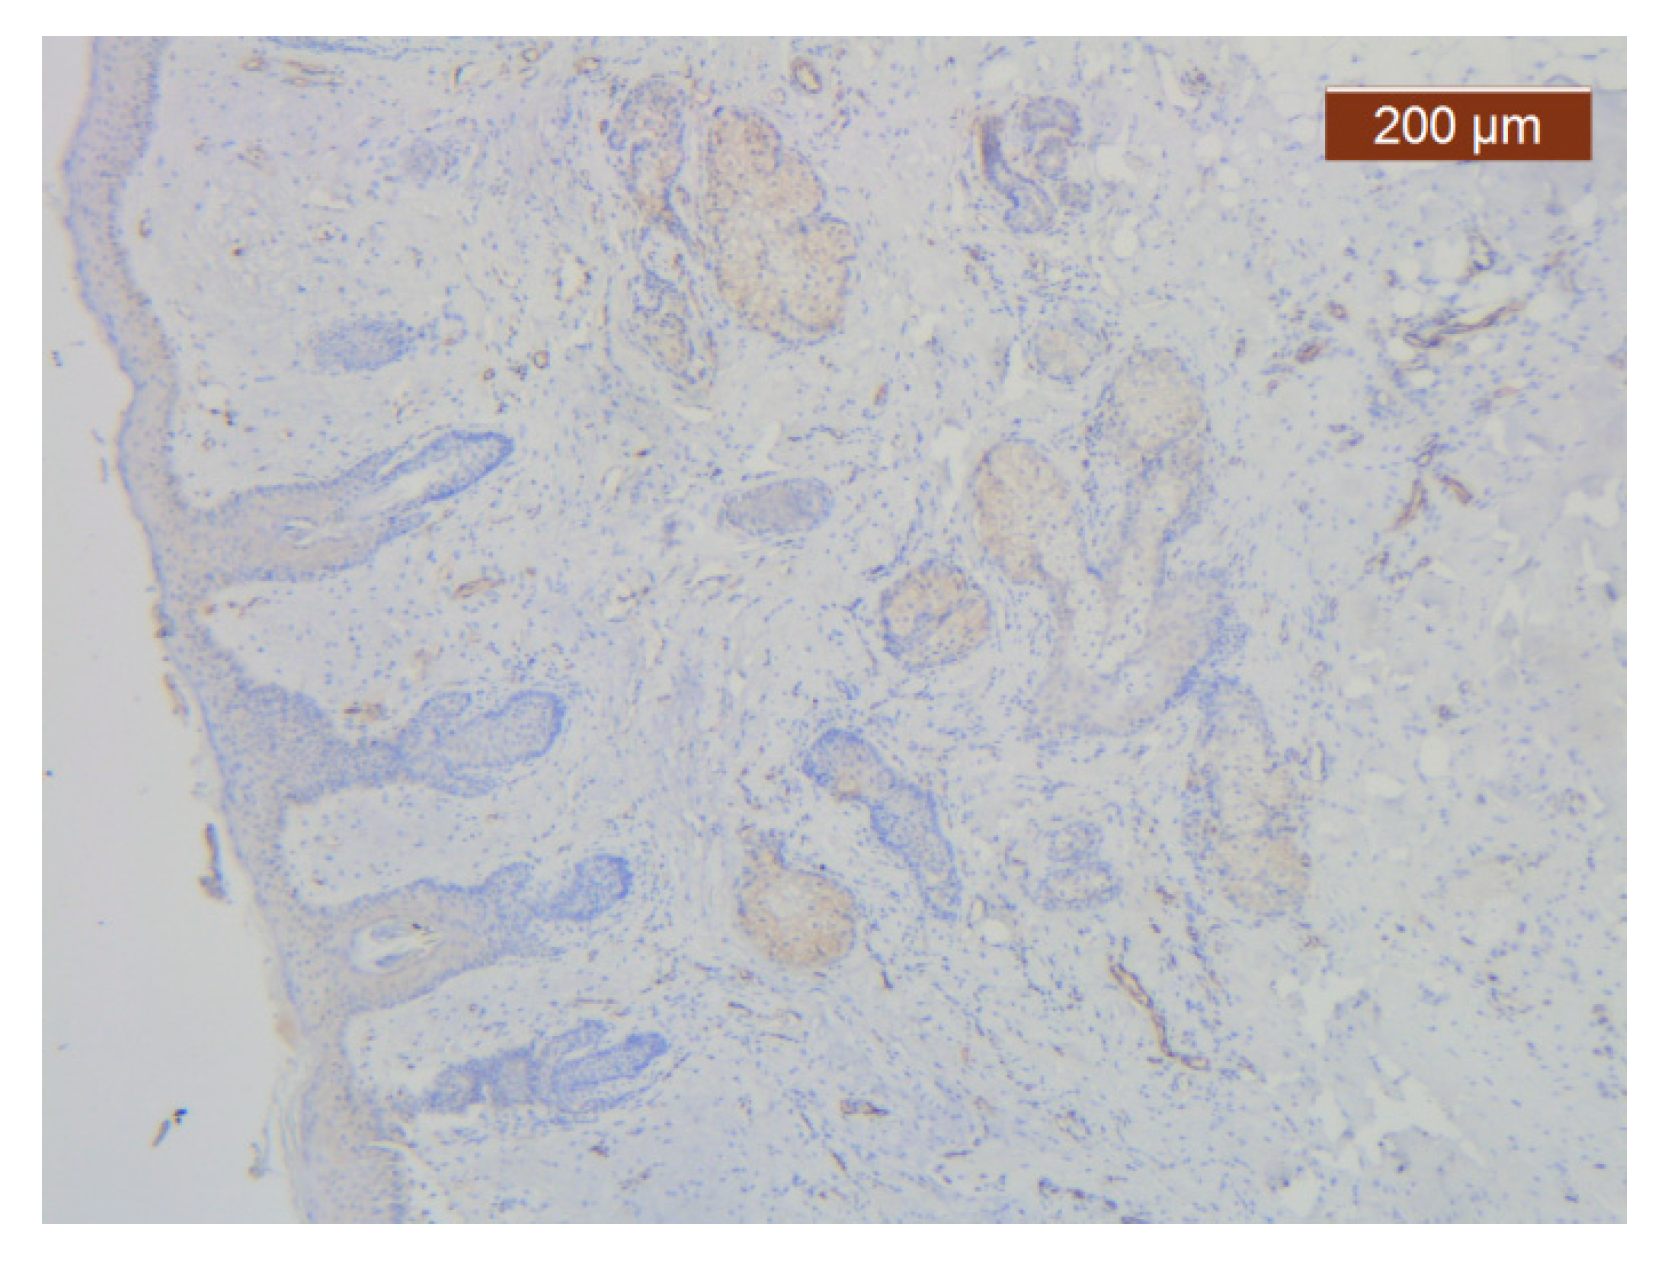

Figure 21. ICAM-2 staining was negative except in blood vessel walls (anti-ICAM-2 ×10 (left), 5 (right)). Staining intensity: weak to moderate.

The region of the nose located medial to the nasolabial fold also presented distinct characteristics at the level of the SMAS bed. The collagen fibers had the densest appearance among the explored regions (Figure 18). This three-dimensional collagen network is distributed toward the superficial dermis and also descends into the deep dermis. At this level, it delimits and seals the large blood vessels (Figure 18, Figure 19 and Figure 20).

With the exception of the walls of the large blood vessel captured on the dissected specimen, the expression of the endothelial marker was zero. It is likely that the nutrition of tissues at this level is achieved by microperfusion from the neighboring regions. (Figure 21).